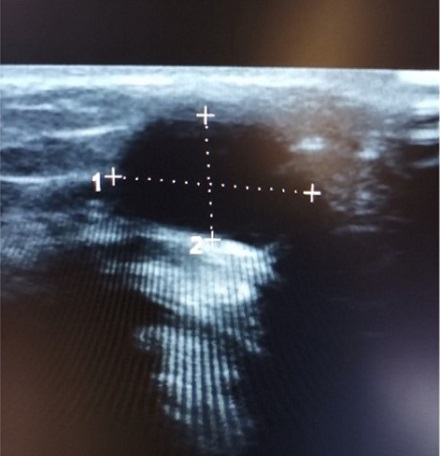

Caso 1. Niño de 7 años con tumefacción laterocervical derecha y fiebre de 2 días de evolución, con buen estado general. Exploración física: tumefacción algo indurada latero-cervical derecha, leve dolor y calor local, sin eritema; el resto normal. Ecografía en AP: dos formaciones bien delimitadas, hipoecogénicas, con flujo Doppler, sin hilio visible (Figura 1). Con sospecha de adenopatía atípica/absceso se deriva al hospital (se realiza analítica, anodina, con PCR baja) y allí se inicia tratamiento con amoxicilina-ácido clavulánico oral. La fiebre y el bulto persisten, al final ingresa, se realiza punción con aspiración de aguja fina con drenaje y en el cultivo crece Nocardia otitidiscaviarum. La evolución ha sido buena, con cotrimoxazol 3 meses. Por ser germen atípico, se ha hecho un amplio estudio inmunológico que ha salido normal.

| Figura 1. Ecografía: dos formaciones bien delimitadas, hipoecogénicas, con flujo Doppler, sin hilio visible |